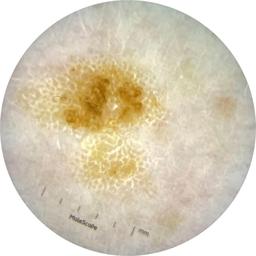

MEL-SELF - Dermoscopic

- Name: MEL-SELF - Dermoscopic

Description:

Dermoscopic lesion images (close-up views of benign and malignant lesions) from the MEL-SELF trial (the Melanoma Self Surveillance trial).